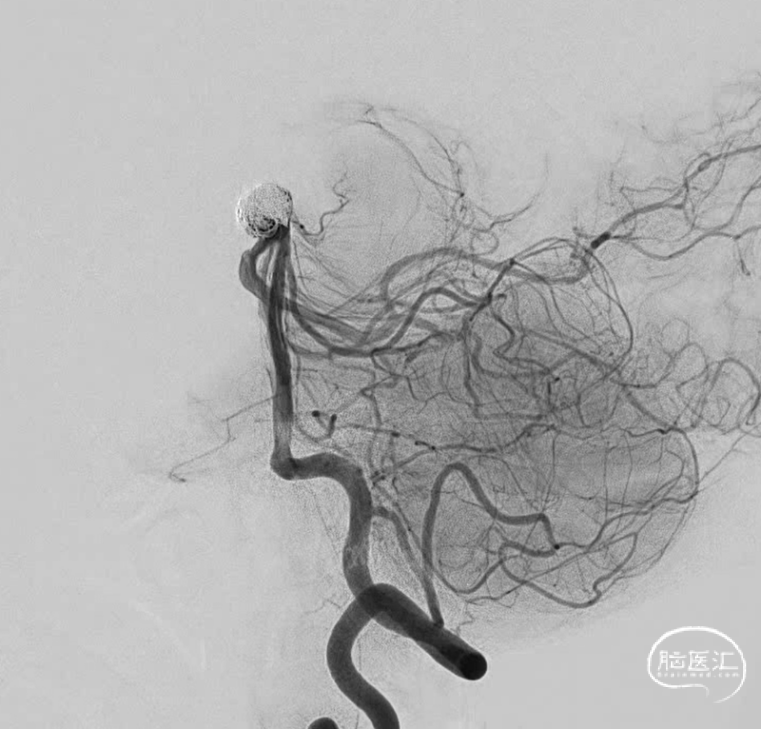

“又是它,大大的瘤,宽宽的颈,实则像个水母”。

虽然棘手,但是也得设计,一个未破裂的动脉瘤。家里比较积极,那就做吧。但是得清楚越安全越好,毕竟没有症状。不管用一个还是两个支架,一切按Y型支架准备。于是乎,双鞘给上。考虑到以往经验,按照自己怎么方便怎么来,右侧鞘安排6F导引导管,操作方便,可以放支架,填弹簧圈。左侧鞘就放个5F导引导管吧,放个支架就完事。

右侧大脑后动脉导管到位,解释一下由于远端血管条件不是太好,因此没有往更远走一些,二则,支架为无头的因此,此位置够用了。

第一个圈盘的还可以,直接支架辅助,一切都很顺利。微导管头的位置按原计划可行。

造影显示,左侧大脑后动脉起始似乎还是受到圈的小小影响,最终决定还是把支架放上。

这个角度,感觉残留一些。

换了个角度,感觉还可以。

标准侧位发现,这个位置有些残留,角度还是比较刁的,不太好到位。虽然有这么一点小遗憾。但是从患者是未破裂动脉瘤,及减少患者风险为第一位的角度上看,还是可以考虑一下。因此毅然决定收手。术后患者安好。